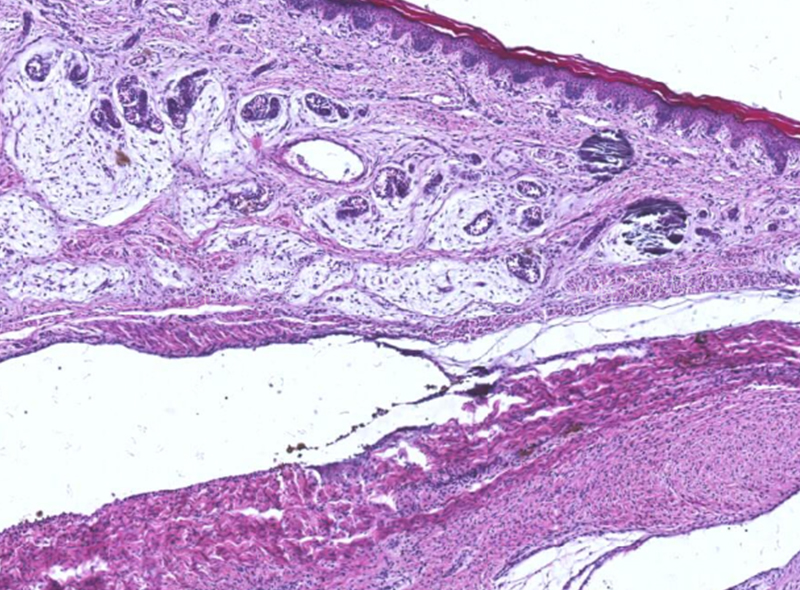

支氣管擴(kuò)張